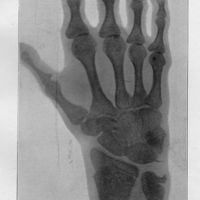

- Progeria; a form of senilism

- Gilford, H.

- 1904

- Practitioner, Vol. 73, pp. 188-217

- Hutchinson - Gilford (syndrome de)